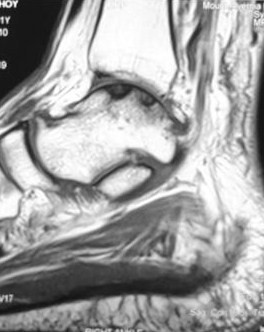

MRI scan showed an osteochondral lesion involving the superomedial aspect of the talar dome.

This diagnosis would have been missed if not for a high index of suspicion and by the use of an MRI scan.